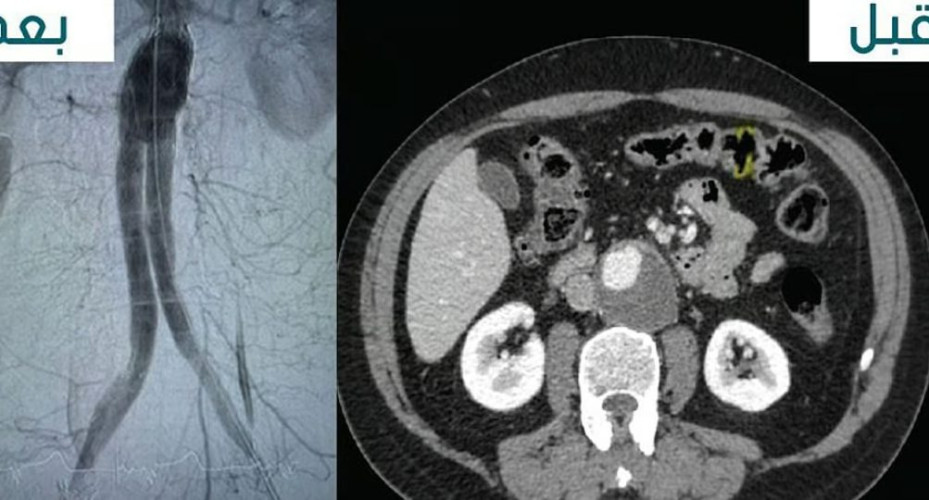

تم بحمد الله وتوفيقه علاج مريض يبلغ من العمر 69 عامًا يعاني من تمدد في الشريان الأورطي البطني بحجم 5 سم في مستشفيات المانع بالخبر، وذلك باستخدام تقنية القسطرة العلاجية.

وتمت العملية عبر شق صغير في الفخذ، مما جنب المريض إجراء الجراحة التقليدية عبر فتح البطن.

أُجريت العملية تحت إشراف د. سامي خليفة، استشاري جراحة الأوعية الدموية، ود. بندر الظفيري، استشاري الأشعة التداخلية، وتعد هذه التقنية المتقدمة بديلاً فعالاً وأقل تدخلاً للجراحة التقليدية، مما يسهم في تقليل فترة التعافي والمضاعفات المحتملة.